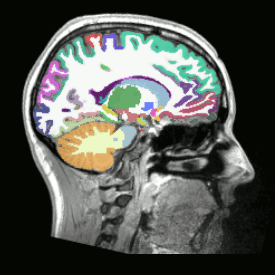

Analyses - Preprocessing

02 Parcellation

Visualization

- Images, masks

- Itksnap

- FSLview

- Freeview

- Tractography, fODF, tensors

- Fibernavigator

- MRview